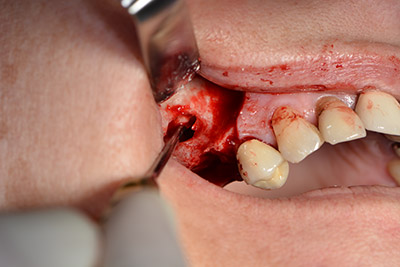

Procedimiento quirúrgico durante el implante

El guiado clásico del corte (crestal, descarga bucal) y la preparación del colgajo mucoperióstico permiten obtener una buena visión global.

En este caso se utilizan implantes Sky (Bredent), cuyo protocolo quirúrgico exige el fresado piloto a unas 1.200 rpm (figura 9).